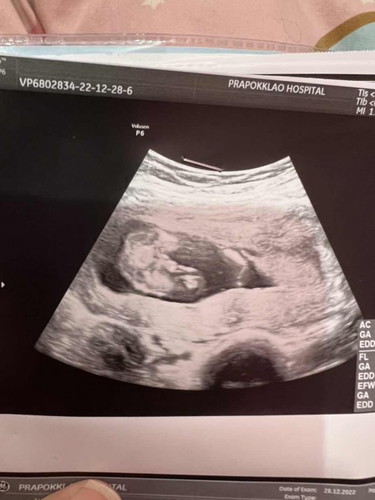

มองออกมั้ยคะว่าเพศอะไรหมอบอกน่าจะผู้ชายมีโอกาสเป็นผู้หญิงมั้ยคะพอดีอยากได้ลูกสาวมากก 15 วีค4วันน .🥹🥹🥹